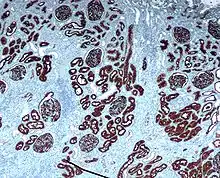

Неприлизин экспрессируется широким спектром тканей, но особенно высокий уровень белка обнаружен в почках. Это частый антиген, обнаруживаемый при остром лимфобластном лейкозе, и является важным маркёром при диагностике заболеваний у человека. Представлен на лейкемических клетках пре-B-лимфоцитарного фенотипа, которые представлены в 85 % всех случаев острого лимфобластного лейкоза[1].

Клетки-предшественники гематопоэтического ряда, экспрессирующие CD10, рассматриваются как общие клетки-предшественники лимфоцитов, то есть лимфобласты, которые способны дифференцироваться в T-лимфоциты, B-лимфоциты или естественные киллеры[2].

CD10 применяется при гематологической диагностике, поскольку белок экспрессирован на ранних B-, про-B- и пре-B-лимфоцитах и в герминативном центре лимфатических узлов[3]. Гематологические заболевания с положительным тестом на CD10/ALL включают ангиоиммунобластную T-клеточную лимфому, лимфому Беркитта, хронический миелоидный лейкоз в бластном кризе (90 %), диффузную B-крупноклеточную лимфому, клетки фолликул лимфоузла (70 %). Острый миелоидный лейкоз, хронический лимфолейкоз, мантийноклеточная лимфома и B-клеточная лимфома маргинальной зоны характеризуются отрицательным тестом на CD10. CD10 отсутсвует на клетках лимфомы, происходящих из зрелых B-клеток[4].